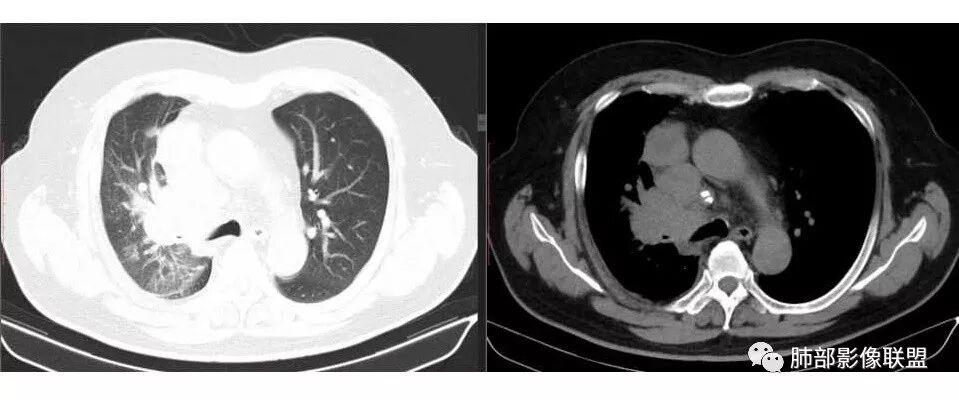

张帅: 患者以肢体无力就诊,既往有吸烟史,胸CT:右肺门占位性病变,密度不均,病灶内病灶内支气管明显狭窄,走行僵硬,病灶边缘光滑,呈浅分叶,未见明显毛刺,对中叶支气管明显挤压。右肺内可见散在片状实变影,前纵隔淋巴结明显肿大,内可见低密度区,2r 4r 7 10r淋巴结明显肿大。诊断考虑恶性方向,肺癌(小细胞)并纵隔肺门淋巴结转移?淋巴瘤?

wonderful: 右肺门巨大占位,支气管均受压变窄,但支气管内无肿瘤,首先考虑小细胞癌

肺门及纵隔多发淋巴结。2L,4R,3区都有肿大淋巴结。

南边:有老师认为,血管前的这个应该是一个胸腺来源的。我觉得不是,为什么不符合胸腺来源呢,就看那个内乳动脉

双侧对比:右侧增粗,提示供血

但在内侧,不是外移

所以我倾向于淋巴结可能

胸腺瘤按理推压外移的多

而且胸腺癌转移不以淋巴结为主,如果淋巴结显著,按理周围侵袭性比较强,淋巴结也应该以附近为主,不应该以肺门为主,不符合引流规律。

支气管狭窄,壁有侵犯

局限性中央间质增厚,考虑癌性淋巴管炎

南边: 而且肺癌,一定受叶段的局限,这一例跨越右肺门,提示多个淋巴结融合

南边: 例如这个病灶,如果是一个孤立的肿块,边界清晰,提示破坏性不强,不应该是包绕支气管,是推移到一边为主,这个表现为包绕,提示是多个病灶融合

1.右肺上叶不规则结节影,右肺门及纵隔多结节并形成巨大块影,密度均匀,沿途支气管明显狭窄。

原发灶小或隐匿,肺门纵隔淋巴结异常增大,所谓“娘小崽大”常见于肺小细胞癌!